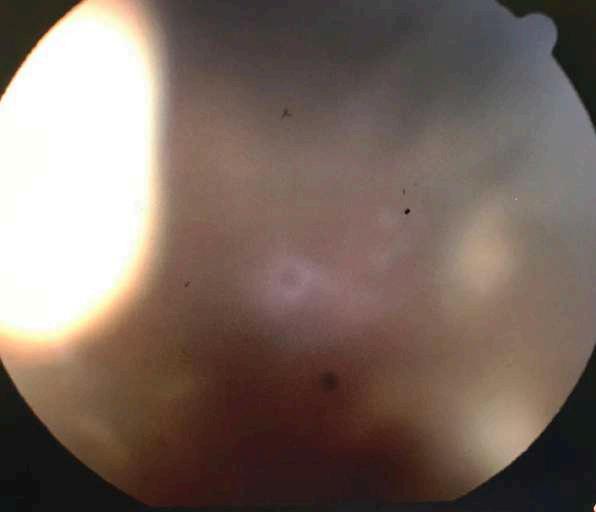

1.F. NECROSIS RETINAL AGUDA BILATERAL (NRA) POR CITOMEGALOVIRUS (CMV)

Caso aportado por Tomás González

NECROSIS RETINAL AGUDA POR CMV

ü La necrosis retinal aguda es una panuveítis, que en el caso descrito a continuación se dio en un pacientede 4 años inmunosuprimido

ü CMV es una causa inhabitual de NRA

ü Puede ser unilateral o bilateral asincrónica Clínica

ü Áreas de necrosis retinales focales, bien delimitadas en la periferia, más allá de la arcada vascular temporal

ü Rápida progresión de la necrosis, circunferencial, cuando no se instaura tratamiento antiviral

ü Evidencia de vasculopatía oclusiva con compromiso arteriolar

ü Reacción inflamatoria vítrea y de la cámara anterior.

ü Otras características menos frecuentes incluyen la neuropatía óptica y escleritis.

Caso clínico

ü Niño de 4 años, con antecedentes de púrpura trombocitopénica amegacariocítica, recibe transplante de progenitores hematopoyéticos. Sin embargo, paciente evoluciona con infección sistémica por CMV por lo que se decide iniciar tratamiento con Foscartet EV (actualemente está en su 7º día de tratamiento).

ü Por lo anterior se solicita evaluación por oftalmología para descartar compromiso ocular.

Examen Físico

AV: no coopera

PIO no registrado

Fondo de ojos:

ü OD: Lesión blanquecina a temporal de la mácula, vecina a fóvea (Imagen A)

ü OI: Lesiones blanquecinas granulares y hemorrágicas en arcada temporal superior (Imagen B)

Torres JP, López JP. Necrosis retinal aguda: una entiedad de adultos en pediatría. Rev Chil Infect 2007; 24(4) 327-330

A B